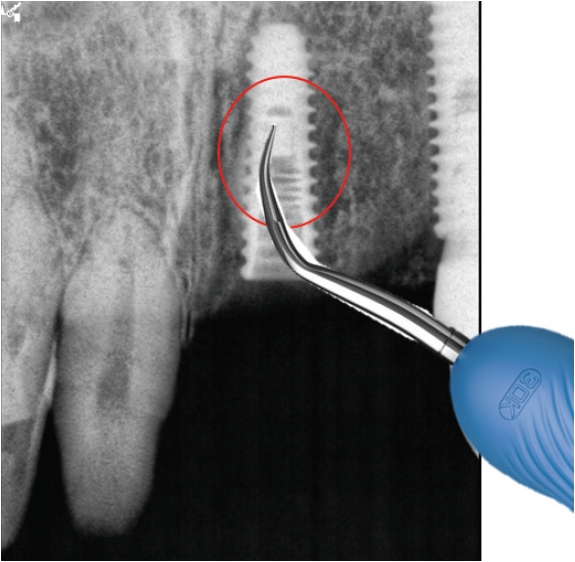

2) 지대주파절편제거

연결나사의 파절보다 빈발하게 발생하는 것이 지대주의 파절인데(Fig. 5) 제거가 잘 되지 않는다. 이때는 다양한 방법으로 제거를 할 수 있으나 최근에는 여러 회사에서 발매되어 나오는 리무버가 있어 제거가 비교적 용이해졌다(Fig. 6).

리무버를 적용할 때 주의할 사항은 역회전으로 고정을 하여야한다는 것이다. 이후에 라쳇이나 토크렌치등으로 잡고 흔들어서 제거해야만 제거가 용이하다. 그럼에도 불구하고 제거에 실패하는 경우에는 bur를 이용하여여 제거하는 수 밖에 없다(Fig. 7).